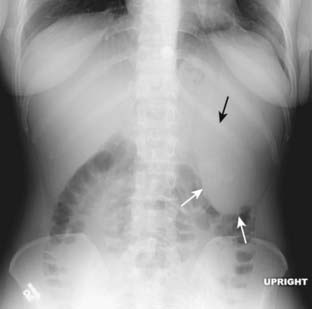

Figure 13-6 Normal upright abdomen.

There for two things to look for on an upright view of the abdomen: air-fluid levels and free intraperitoneal air. Normally, there is an air-fluid level in the stomach (solid black arrow). There may be short, air-fluid levels present in a few nondilated loops of small bowel (black circle). There are usually very few or no air-fluid levels seen in the colon. Free air, if present, should be visible just below the hemidiaphragm (dotted black arrow) and would be easier to recognize on the right than on the left.